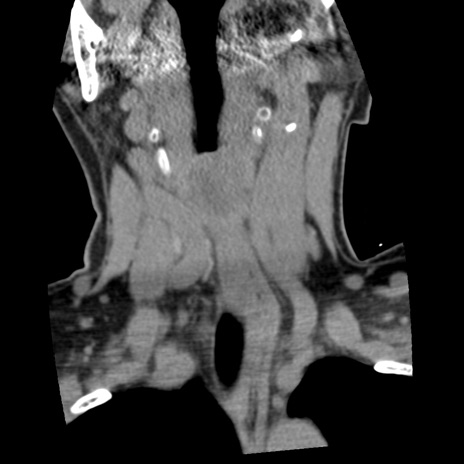

症例50 頚椎CT(冠状断像)

【症例】60歳代女性

【主訴】後頭部〜右後頸部にかけての痛み

【現病歴】本日飲食店でコーヒーを飲んでいたところ、突然後頭部〜右後頸部にかけて痛みが出現し、右上肢の感覚障害を伴ったため救急要請。

【身体所見】脳神経学的に明らかな異常所見を認めず。右上肢に軽度の感覚障害あり。

異常所見と診断は?